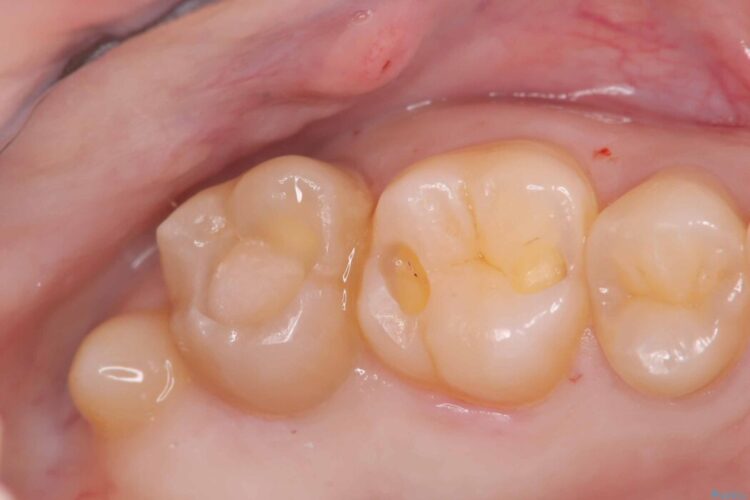

まずは古い詰め物と虫歯を丁寧に除去します。

除去後は、再発リスクを抑え長期的な安定を図るために、適合精度が高く劣化しにくいセラミックインレーによる修復を計画しました。